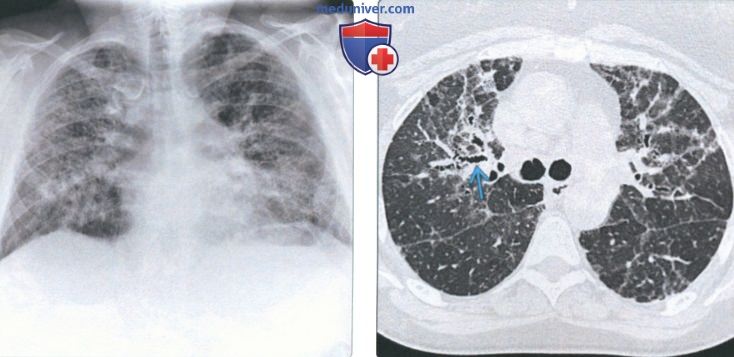

Рентгеновские снимки при пневмоцистной пневмонии